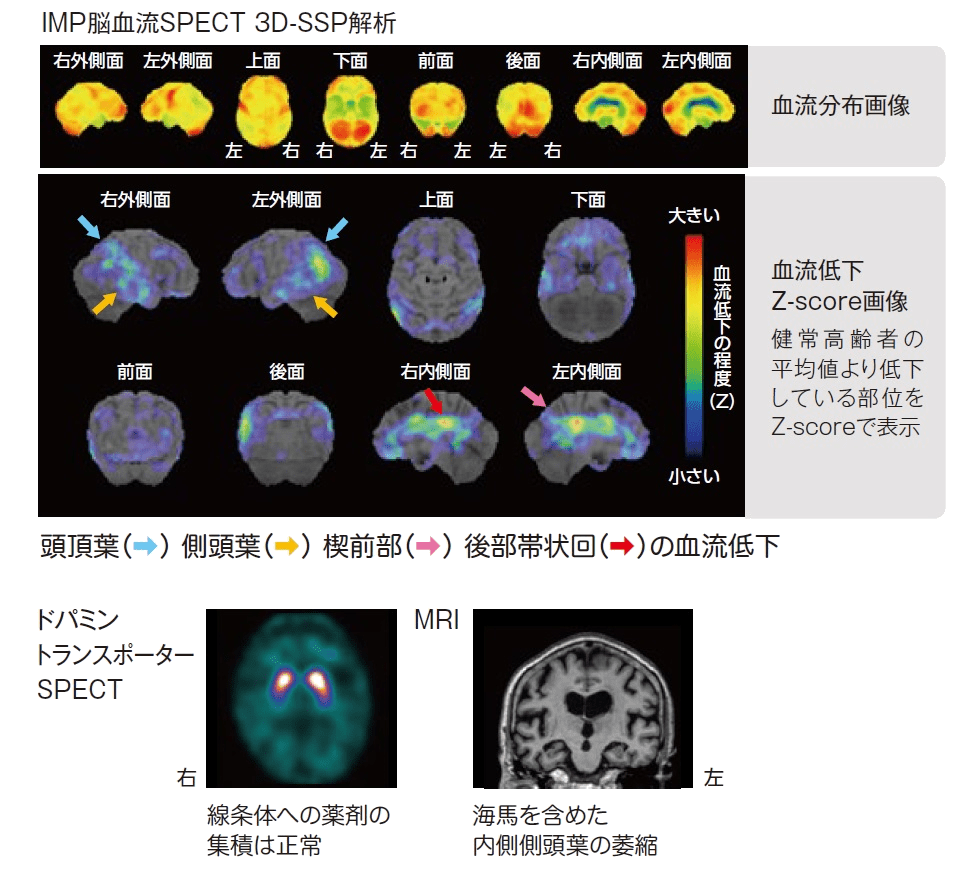

脳のSPECT 機能画像のよみ方・使い方 脳血流SPECT画像 認知症原因疾患ごとの血流分布と読影の注意点1の詳細情報

脳血流SPECT画像 認知症原因疾患ごとの血流分布と読影の注意点1。脳血流SPECT統計解析ソフトウェア (e-ZIS) が新しくなりました。SPECT検査 横浜市。脳のSPECTに関する機能画像の解説と使用法を詳述した専門書。RI検査(SPECT:スペクト検査)|放射線科|診療科のご案内。- タイトル: 脳のSPECT 機能画像のよみ方・使い方- ISBN: 9784524201716- 価格: 15000円ご覧いただきありがとうございます。ぜりー様、専用。